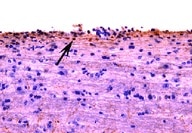

HSP70/HSPA1A in Human Liver Cancer Tissue. HSP70/HSPA1A was detected in immersion fixed paraffin-embedded sections of human liver cancer tissue using Mouse Anti-Human/Mouse/Rat HSP70/HSPA1A Monoclonal Antibody (Catalog # MAB1663) at 25 µg/mL overnight at 4 °C. Tissue was stained using the Anti-Mouse HRP-DAB Cell & Tissue Staining Kit (brown; Catalog # CTS002) and counterstained with hematoxylin (blue). View our protocol for Chromogenic IHC Staining of Paraffin-embedded Tissue Sections.